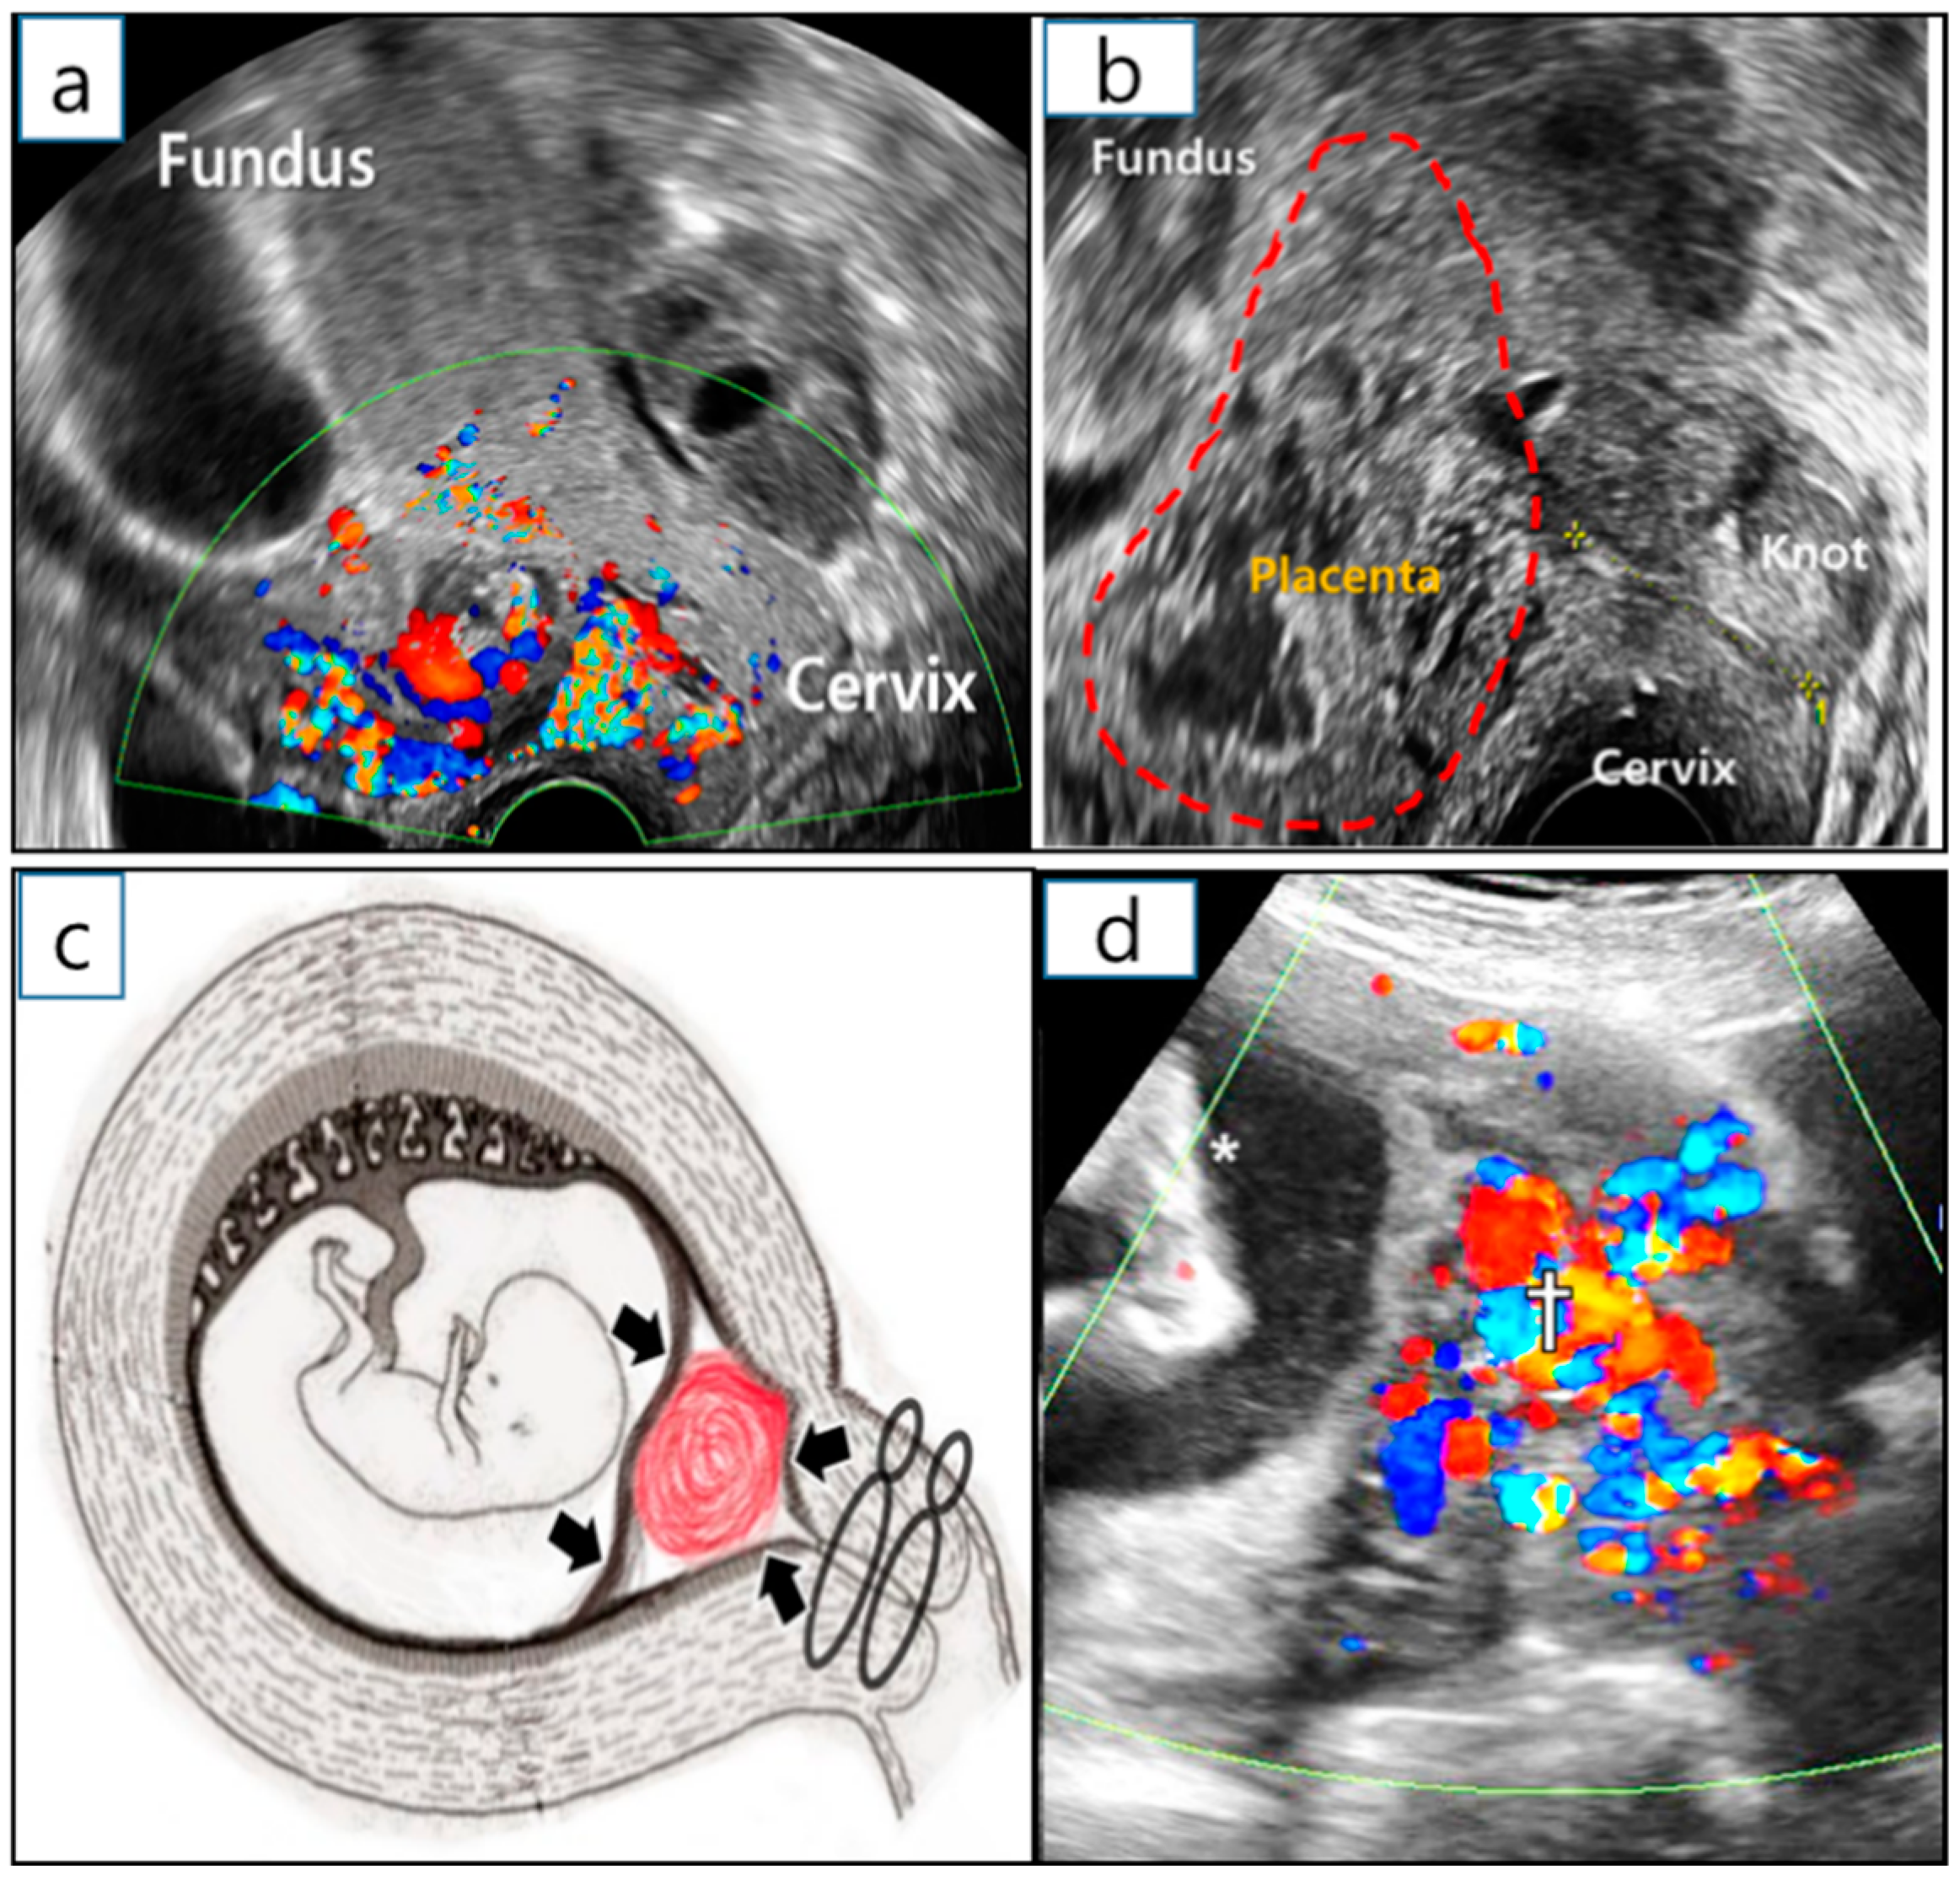

A sonographic examination at 10 GW revealed that the placenta around the reduction site had grown into the uterine cervix, resulting in intermittent vaginal spotting and a shortening of the cervical length. Considering a cervical length of less than 10 mm and the protrusion of the remnant placenta into the internal os (Figure 4a), a uterine cervical cerclage was inserted at 12 GW by placing the cervical intruding placenta inside the uterine cavity. The purpose of the cerclage was to control the growth of the remaining placenta in the CSP, as well as vaginal bleeding (Figure 4b,c). McDonald operation with double ligations using braided polyester thread (EthibondTM, Ethicon, New Jersey were implemented in the cervical cerclage [4]. A previous retrospective study reported that the braided thread suture in the cervical cerclage showed an improvement in neonatal survival, the prevention of preterm birth before 28 GW, less PPROM, and maternal febrile morbidity, compared to Mersilene tape (Mersilene™, Ethicon, Somerville, NJ, USA). [5]. Ultrasonography at 24+3 GW showed dilated and tortuous blood vessels encompassing the lesion (10 × 6 × 3 cm3 in volume), suggestive of an enlarged arteriovenous malformation (AVM) (Figure 4d). During the antenatal period, there were no severe complications, including preterm labor and short cervical length.

Figure 4. Management of arterio-venous malformation after selective CSP embryo reduction. (a) Ultrasonography to visualize RGT with cervical shortening at 10+3 GW before cervical cerclage. The RGT went into the uterine cervical internal os. (b) Transvaginal ultrasonography at 12+3 GW after the cerclage. (c) Effect of cervical cerclage role on HCSP management (details are written in the discussion section). (d) Ultrasound examination at 24+3 GW. Enlarged arterio-venous circulation was observed in the demised CSP (†); asterisk (*) indicates the fetal foot. CSP—cesarean scar pregnancy; GW—gestational weeks; RGT—remnant gestational tissue.